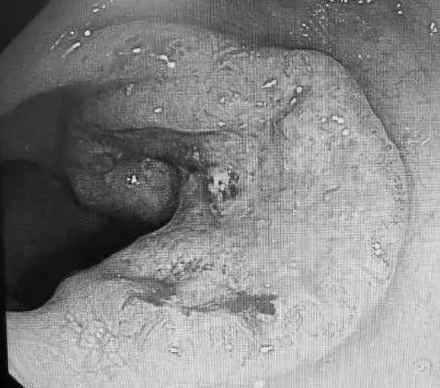

然后进行了肠镜检查,就在继续进镜,在乙状结肠距离肛门17~20厘米的地方,发现了一个直径3厘米的溃疡样病变,凭借医生经验判断,应该是癌!

距肛门17-20厘米处,3厘米之溃疡性病变

于是马上安排这处病变取了组织,送去做病理检查确诊为乙状结肠癌。由于老人发现得比较早,如果通过外科手术切除,加上综合治疗,可以获得很好的治疗效果。